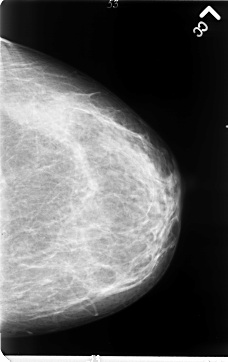

B_3061_1.LEFT_CC

LEFT_CC LINES 4696 PIXELS_PER_LINE 2952 BITS_PER_PIXEL 12 RESOLUTION 50 NON_OVERLAY